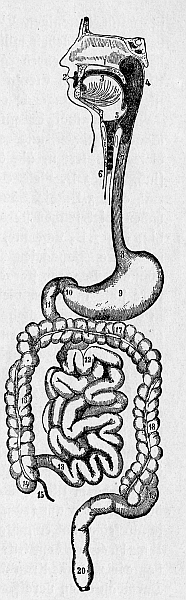

Wir sind alle von Bazillen bevölkert, von Millionen und Abermillionen Bazillen, die in unserem Darme wohnen. Namentlich in dem unteren Teile des Darmrohres, im Dickdarm, sind die Bakterien[1] wohl zu Hause. Wie ungeheuer viele es sein mögen: wenn man bedenkt, daß wir insgesamt an die sieben Meter Darm, und davon etwa anderthalb Meter Dickdarm herumtragen (Abb. 1)! Wollten wir die Bakterien zählen, die bloß in einem allerkleinsten Krümelchen unseres Darminhaltes drin sind, wir kämen schon in die Millionen hinein. Über hunderttausend Milliarden Bazillen – also eine Million mal Million und dann noch mal hundert – werden es nach allerlei Berechnungen wohl schon sein, die wir in unserm Darm insgesamt beherbergen. Ein ganzes Drittel von dem, was wir aus dem Darm an einem Tage entleeren, sind lauter Bazillen!

Abb. 1. Schema des Verdauungsrohres. 1 Gaumen, 2 Mundspalte, 3 Zunge, 4 Schlund, 5 Kehldeckel, 6 Luftröhre, 7 Speiseröhre, 8 Mageneingang, 9 Magen, 10 Magenausgang, 11 Zwölffingerdarm, mit dem der Dünndarm beginnt, 12 Dünndarmschlingen, 13 Übergang des Dünndarms in den Blinddarm, 14 Blinddarm, mit dem der Dickdarm beginnt, 15 Wurmfortsatz, 16, 17, 18 Dickdarm, 19, 20 Enddarm. Nach Rauber.